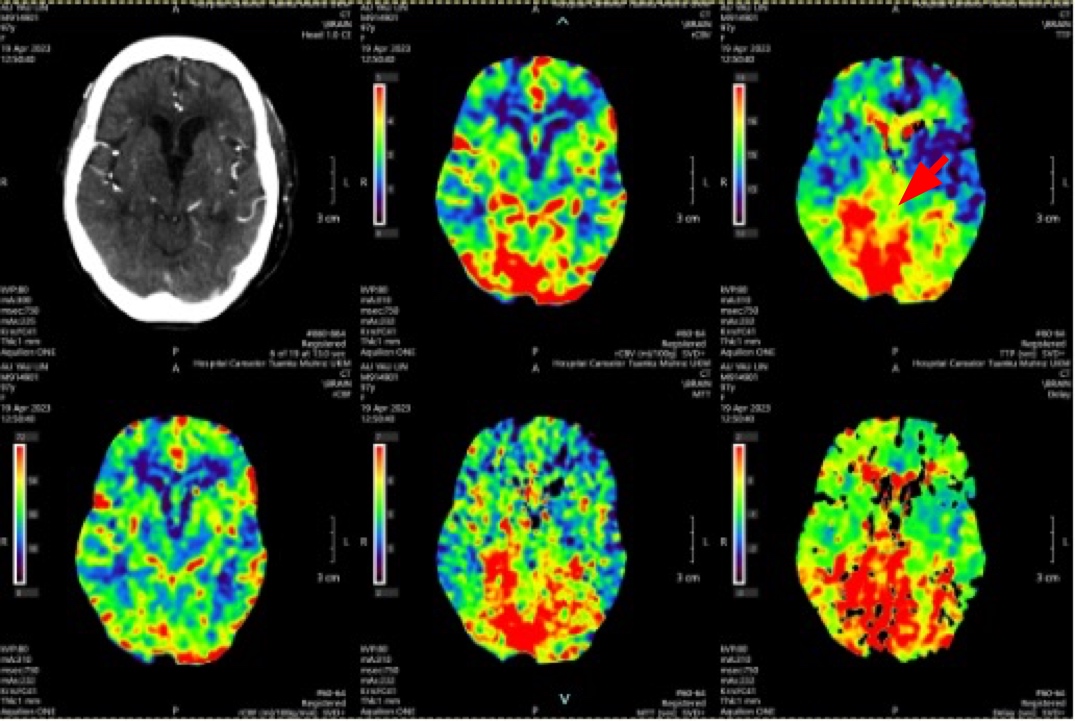

A delay in recognising acute posterior circulation infarct (POCI) can cause a delay in treatment and high mortality rate. There has been an increasing trend in incidence of stroke among the elderly. Treating acute stroke in elderly has been challenging due to the lack of data on the functional outcome and mortality risk. A 97-year-old woman had left sided weakness upon waking up from sleep and dizziness two days prior. Upon arrival, her Glasgow Coma Scale (GCS) was E3V4M6, BP 162/112 mmHg, NIHSS score 10, left sided power 3/5 and right sided power 4/5. Her computed tomography (CT) angiography brain showed P2 segment of right posterior cerebral artery and distal basilar artery thrombosis, with a posterior circulation territory mismatch. Thrombolysis was given immediately. She was discharged with NIHSS 5, GCS E4V5M6 and power bilateral limbs 4/5. She was put on lifelong Apixaban for stroke prevention and underwent post-stroke rehabilitation. The time of occlusion was decided based on the time a patient was last seen well. Studies have shown that patients aged 80 years and above presenting within 3-4.5 hours from symptoms, perform well with both intravenous thrombolysis and thrombectomy, with no increased risk for intracranial hemorrhage and death.

Kelewatan dalam mengenal pasti 'posterior circulation infarct' akut boleh menyebabkan kelewatan dalam rawatan dan kadar kematian yang tinggi. Terdapat peningkatan dalam kejadian strok di kalangan orang tua. Rawatan strok akut untuk orang tua sangat mencabar disebabkan oleh kekurangan data mengenai komplikasi dan hasil fungsi mereka. Seorang wanita berusia 97 tahun mengalami kelemahan di bahagian kiri badannya ketika bangun dari tidur dan pening dua hari sebelumnya. Apabila tiba di hospital, skala 'Glasgow Coma' (GCS) beliau adalah E3V4M6, tekanan darah 162/112 mmHg, skor NIHSS 10, kekuatan di bahagian kiri badan 3/5 dan di bahagian kanan badan 4/5. Pemeriksaan tomografi komputer (CT) otak menunjukkan trombosis pada segmen P2 arteri serebrum posterior sebelah kanan dan arteri basilar distal, dengan 'posterior circulation mismatch'. Trombolisis diberikan segera. Beliau dibenarkan discaj dengan NIHSS 5, GCS E4V5M6 dan kekuatan pada kedua-dua anggota badan 4/5. Beliau diberi Apixaban seumur hidup untuk pencegahan strok dan menjalani rehabilitasi pasa-strok. Masa thrombosis dianggarkan berdasarkan masa terakhir pesakit kelihatan sihat. Kajian telah menunjukkan bahawa pesakit yang berusia 80 tahun ke atas yang hadir ke hospital dalam masa 3-4.5 jam selepas gejala, menunjukkan pemulihan yang baik dalam aspek fungsi anggota badan jika dirawat dengan trombolisis intravena atau trombektomi, tanpa peningkatan risiko pendarahan otak dan kematian.